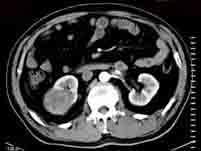

诊断肾肿块最好的检查方法是()A.B超B.CTC.IVUD.腹平片E.肾图

问题 诊断肾肿块最好的检查方法是()

选项 A.B超 B.CT C.IVU D.腹平片 E.肾图

答案 B